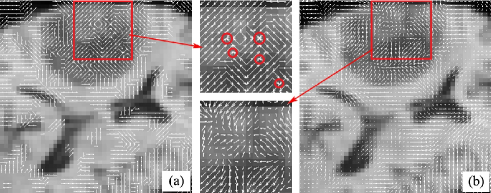

Fig. 2. illustrats the discrete displacement vectors reconstructed for every pixel in tumor resection region using local kernel regression. Because block matching results inherently contain incorrect matches, which are exacerbated by the outliers in the tumor resection region. As a result, the conflicts between neighboring displacement vectors (see the several red circles shown in Fig. 2(a)) widely exist in the discrete displacement field for the tumor region. Those displacement conflicts can easily introduce the topology change of structures, such as tearing and distorting. Fortunately, all the displacement vector conflicts are removed or smoothed by the local kernel regression in Fig. 2(b), where the displacement vectors having opposite directions fully disappear with the displacement magnitudes simultaneously being smoothed. Next, to match local structures in the presence of outliers, we design structural adaptive kernel functions and robust weighing schemes for the moving windows/kernels to further boost the accuracy and robustness of the local deformation reconstruction.